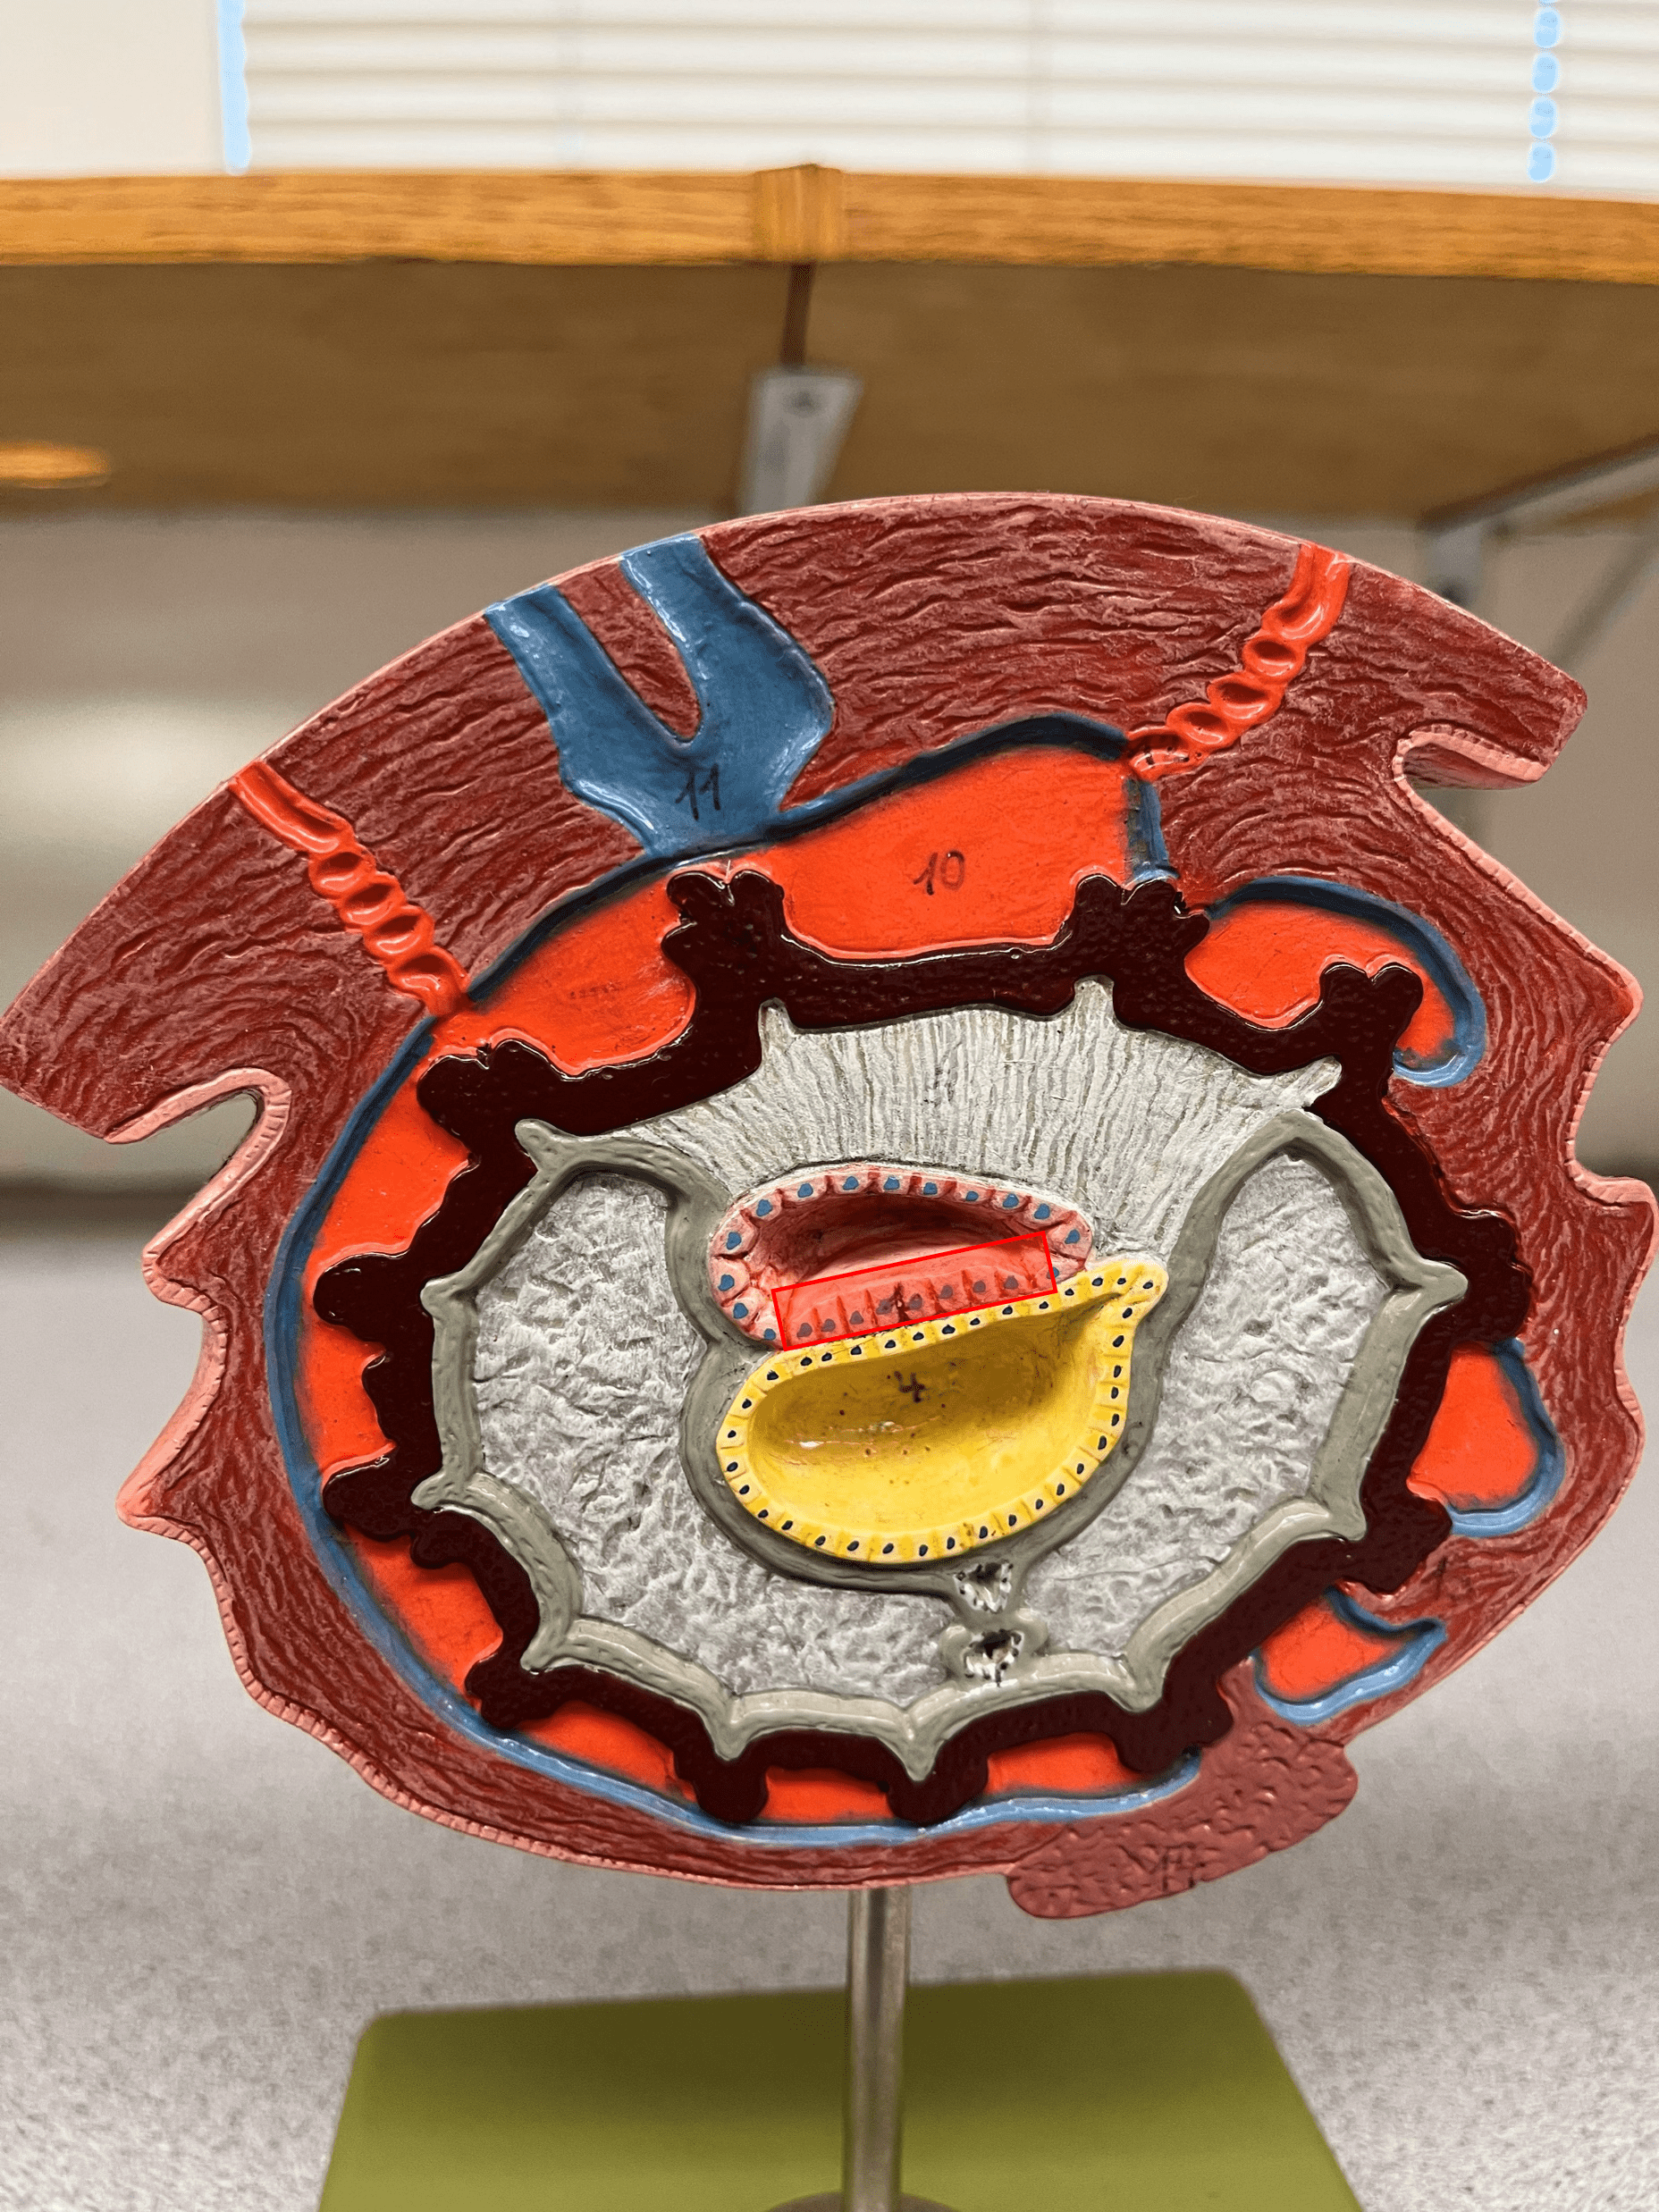

New cards

14

• Also known as a placental sinus.

New cards

20

21

22

• Becomes the fossa ovalis.

• Shortcuts blood from the pulmonary trunk to the aorta, bypassing the pulmonary circuit.